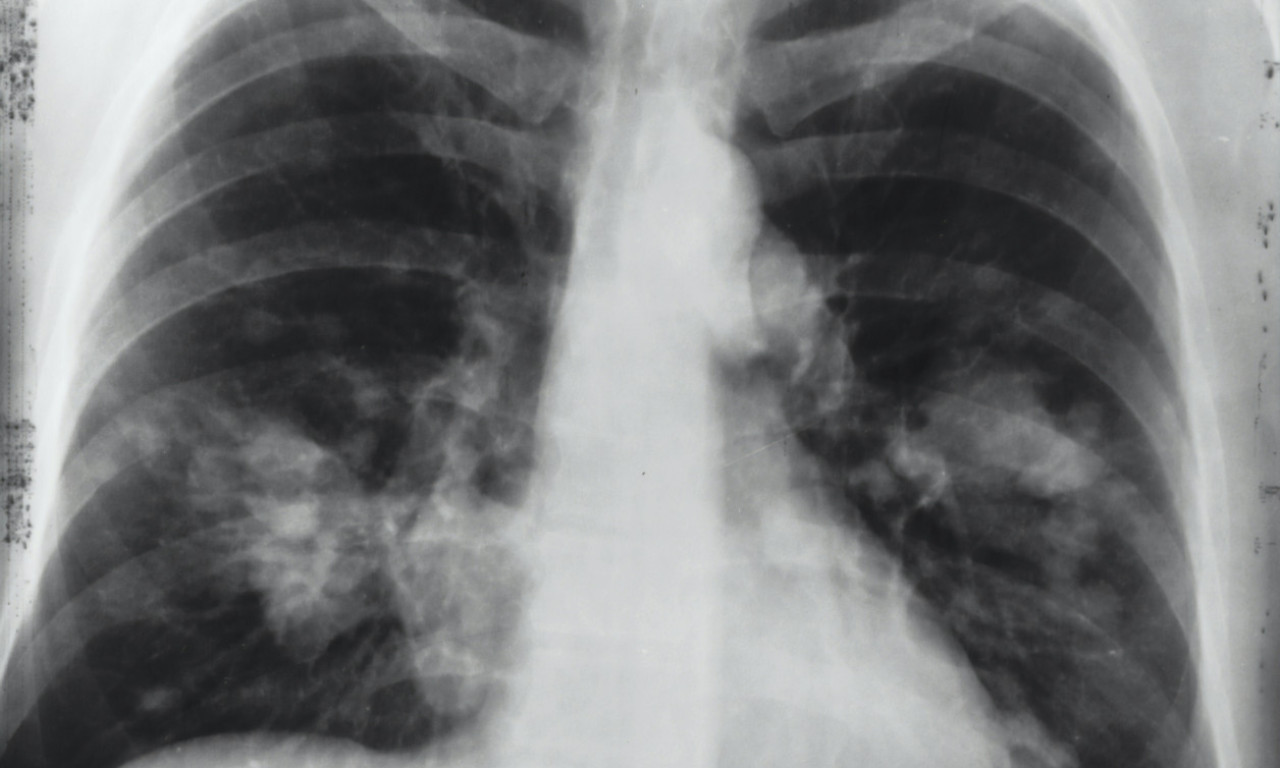

ALARMANTNI PODACI U SRBIJI! Od RAKA PLUĆA oboli 7.000 SRBA godišnje, što nas stavlja na drugo mesto u Evropi

Podatak koji ohrabruje je da se posle pojave prvih simptoma većina pacijenata odmah obrati lekaru

CRNA STATISTIKA: 70% obolelih RAK PLUĆA otkrije tek kad su ŠANSE ZA IZLEČENJE MINIMALNE, ovo je NAJVEĆI PROBLEM

Doktor je objasnio koje metode lečenja postoje u Srbiji i na koji način se određuje da li će pacijent biti podvrgnut inovativnom lečenju